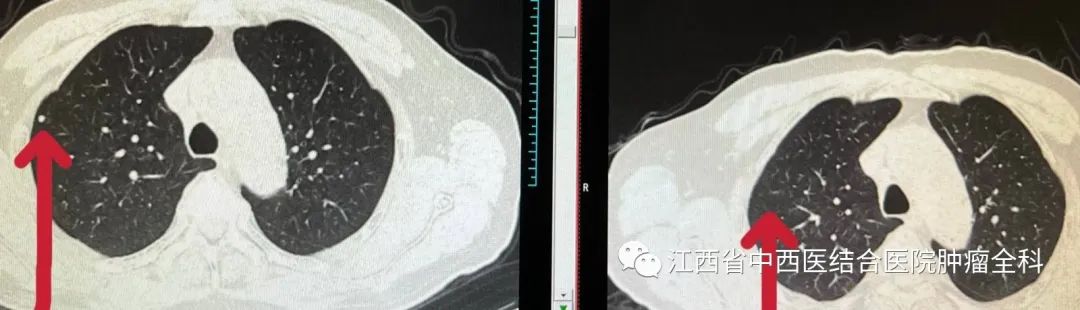

图5-7:2022年2月07日与2022年5月17日胸部CT结节影治疗前后对比

胸部CT: 双肺多发结节转移灶较前缩小,部分消失。

胸部CT: 双肺多发微结节灶已消失。

患者老年男性,原发性肝细胞癌切除术后靶向治疗1年余,发生肺、腹腔和骨多发转移,合并酒精性肝硬化,PS评分1分。 患者应用卡瑞利珠单抗治疗2周期后AFP开始明显下降,肺部结节缩小,部分消失;4周期后AFP降至正常范围,肺部结节消失,脾脏前缘膈下结节、骨转移并侵犯左侧髂腰肌、臀小肌、臀小中肌病灶范围较前明显缩小,总体疗效达到大PR。 治疗期间出现的TRAE(治疗相关不良事件)为轻度(1级),包括转氨酶升高,经对症处理后好转。